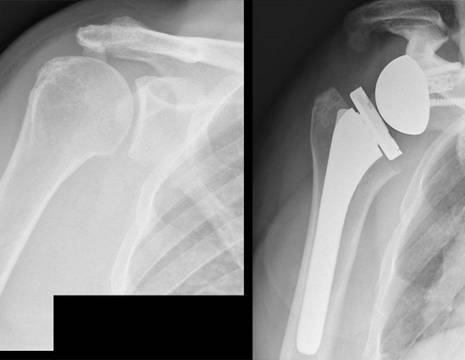

La RADIOGRAFIA può mostrare il posizionamento dei mezzi di ancoraggio all’interno dell’osso e permette una valutazione delle strutture ossee della spalla. La RISONANZA MAGNETICA (RMN) è sicuramente l'indagine di scelta per escludere una sospetta recidiva di lesione tendinea dopo un intervento di riparazione della cuffia dei rotatori. La RMN consente di valutare il ventre muscolare, la lunghezza e la qualità del tendine ed altre strutture intra-articolari che possono causare sintomi.  Vi possono infatti essere patologie concomitanti come capsulite adesiva, artrosi dell'articolazione acromioclavicolare o gleno-omerale, patologie del capo lungo del bicipite, lesioni del nervo soprascapolare e patologie della colonna cervicale.

PROTESI DI SPALLA PER RECIDIVA DI LESIONE CUFFIA DEI ROTATORI

L’intervento di protesi di spalla inversa può essere indicato in pazienti con lesione irreparabile della cuffia dei rotatori, con o senza artrosi. I criteri di non riparabilità tendinea sono soprattutto radiografici (retrazione di grado elevato del tendine, degenerazione in grasso della maggior parte del muscolo, decentramento dell’epifisi omerale sulla glenoide) ma anche clinici: una SPALLA PSEUDOPARALITICA (flessione anteriore della spalla < a 90°) può essere trattata efficacemente soltanto con un intervento di protesi inversa alla spalla. La ripresa della funzionalità alla spalla è buona con questo intervento e la sopravvivenza dell’impianto protesico può arrivare al 93% dopo 10 anni.

Vedi approfondimento intervento di protesi inversa di spalla